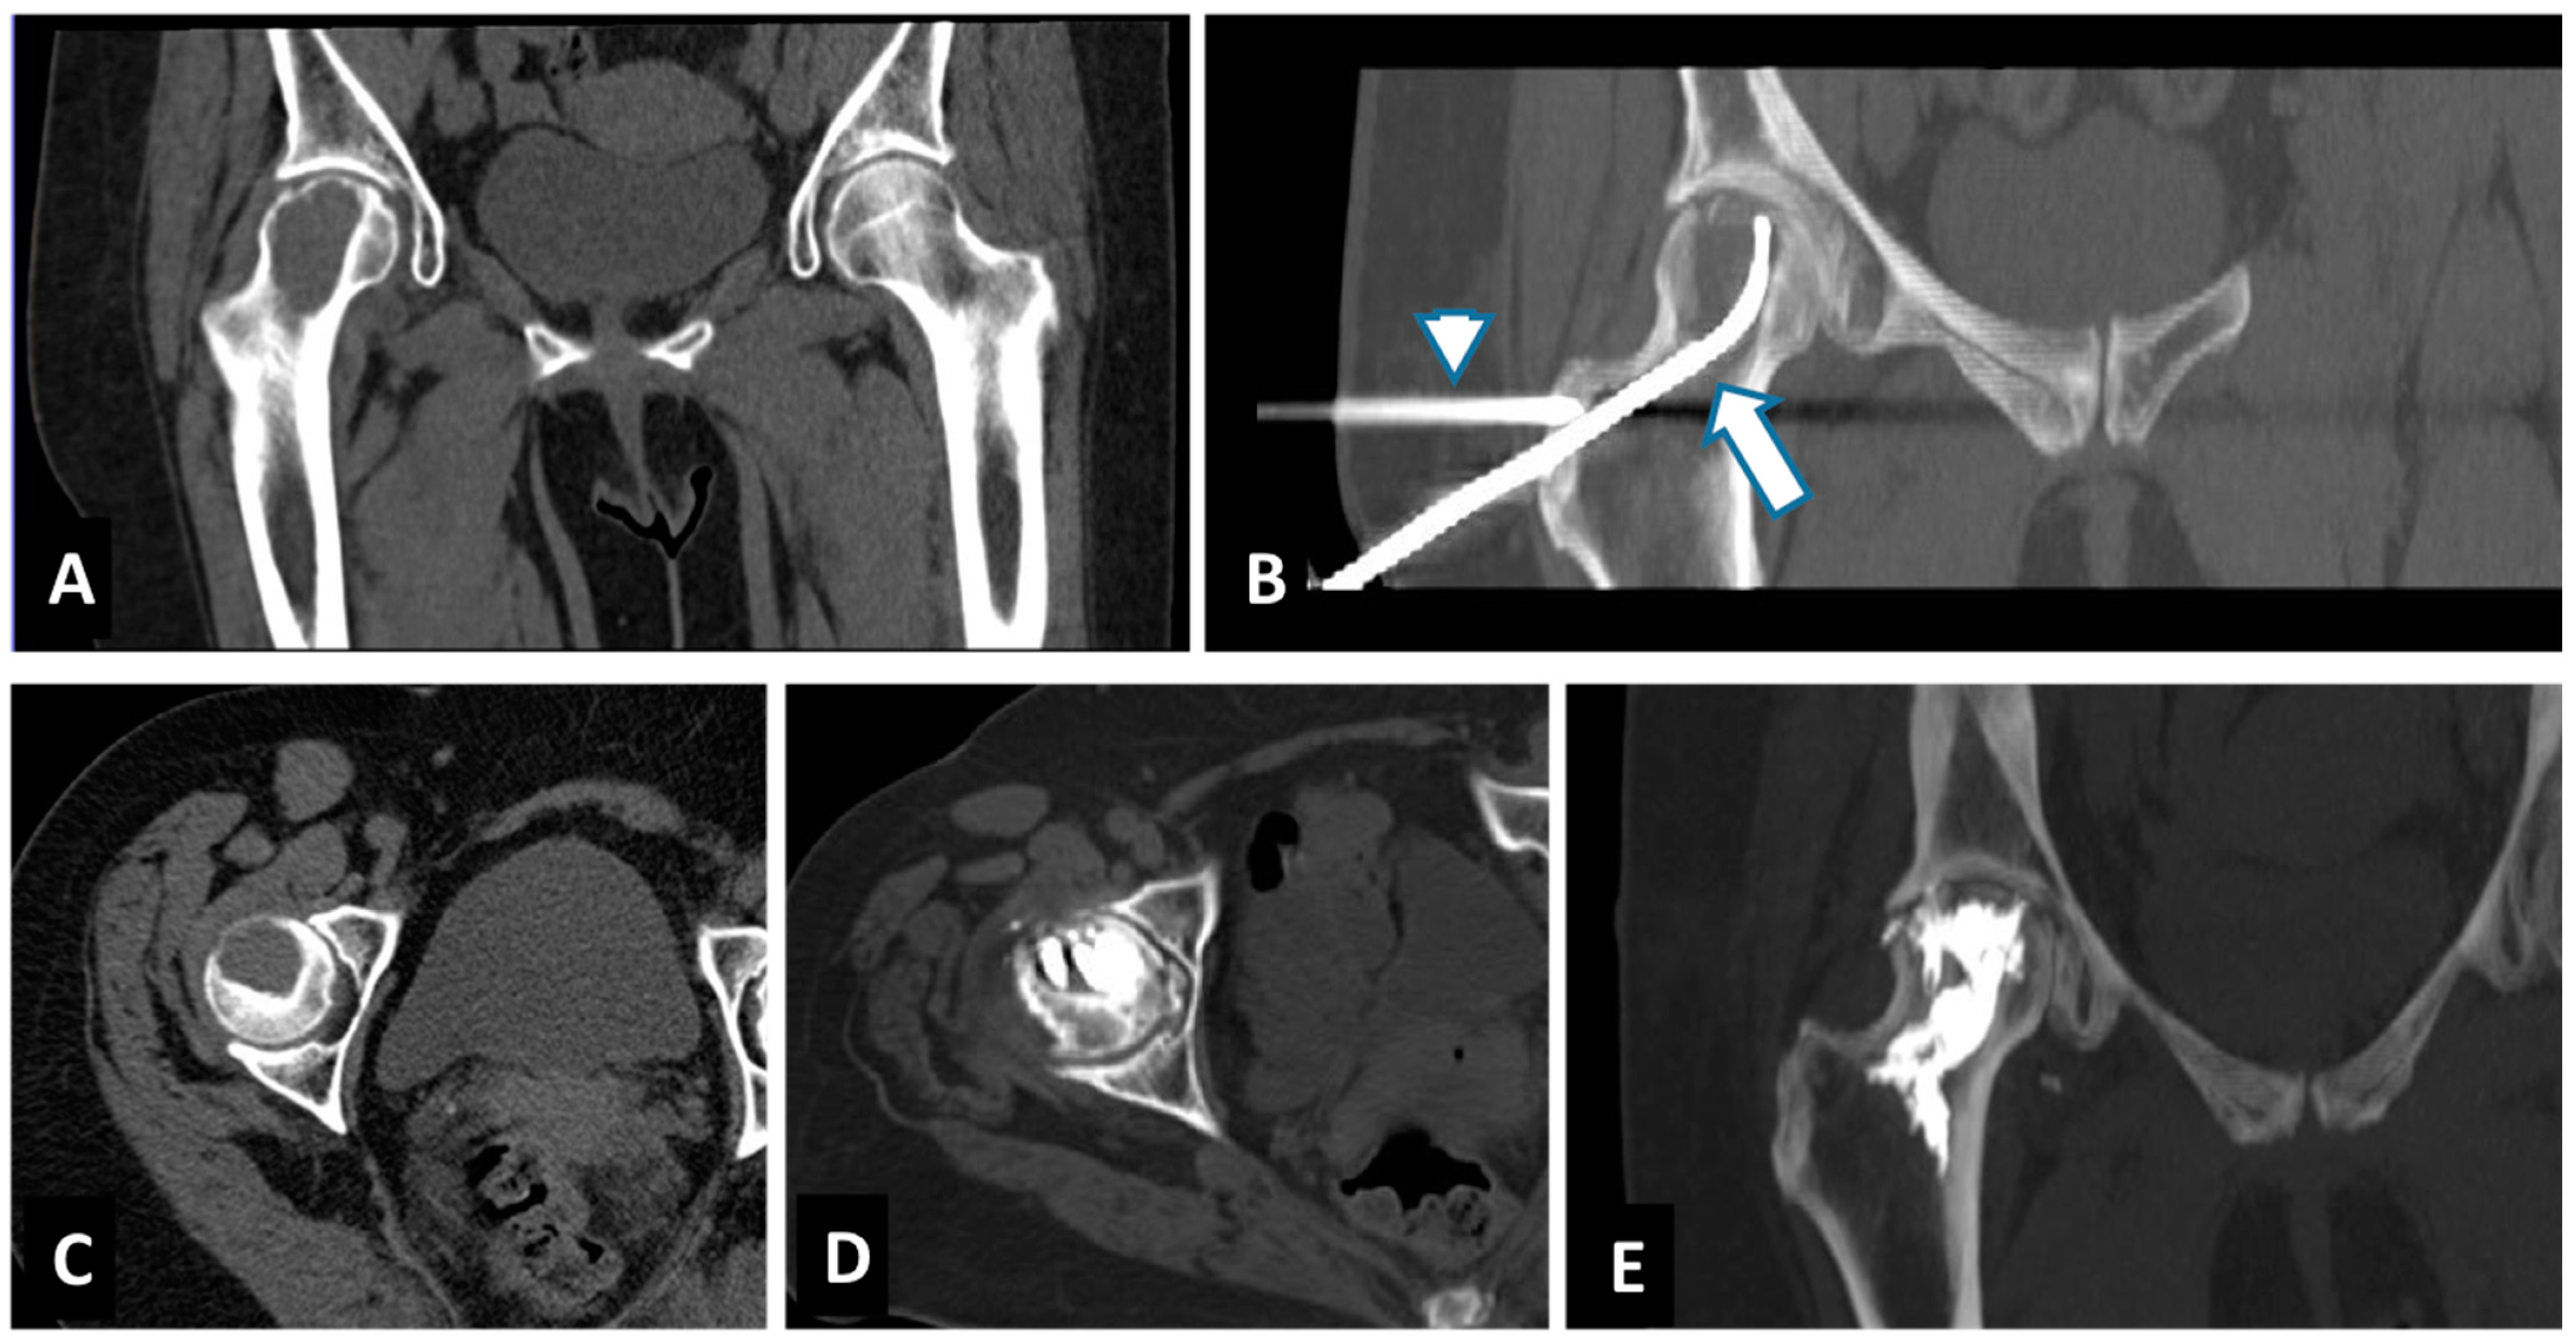

2.2. Radiofrequency Ablation (RFA) and Cementoplasty Procedure

- Wallace, A.N.; Huang, A.J.; Vaswani, D.; Chang, R.O.; Jennings, J.W. Combination acetabular radiofrequency ablation and cementoplasty using a navigational radiofrequency ablation device and ultrahigh viscosity cement: Technical note. Skelet. Radiol. 2016, 45, 401–405. [Google Scholar] [CrossRef]